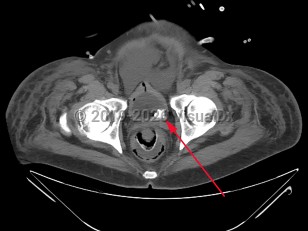

Urinary bladder calculus

The decreased incidence of bladder calculi is largely because the 2 conditions principally associated with bladder stones, urinary stasis (most commonly due to benign prostatic hyperplasia [BPH]) and urinary tract infections (UTIs), are now more easily and frequently treated. BPH, once only effectively treated with surgery, is now frequently effectively and more easily treated with a combination of alpha blockers, 5-alpha reductase inhibitors, or transurethral resection. Consequently, the number of men suffering from chronic urinary retention has significantly decreased. Urinary stasis in the setting of neurogenic bladder is also a common etiology of bladder stone formation.

When urine is chronically retained in the bladder, any nidus, such as a small fragment of a stone passed from the ureter, a bladder diverticulum, or a foreign body such as a ureteral stent or Foley catheter, can serve as a site for the precipitation and deposition of uric acid. In most retrospective studies of bladder stone composition, nearly all stones (as many as 80%) are entirely composed of uric acid, and most of the remainder contain a substantial portion of uric acid. Interestingly, neither gout or hyperuricemia appear to be contributory factors in the formation of bladder calculi. This is qualitatively different than nephrolithiasis, which in the United States is primarily due to calcium oxalate or calcium phosphate stones.